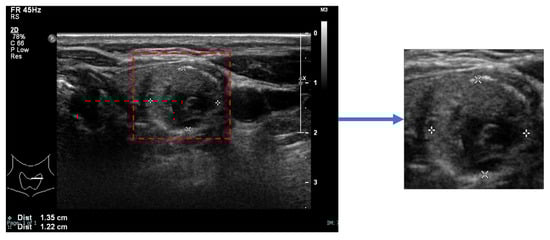

An image of each nodule, detected and segmented by StableSeg GANs [24] in an ultrasound image, was cropped with a 5% margin and resized to 512 × 512, as shown in Figure 2.

Figure 2. Preparation of a nodule image. The nodule, segmented using StableSeg GANs, was cropped with a 5% margin and then resized to 512 × 512 pixels.